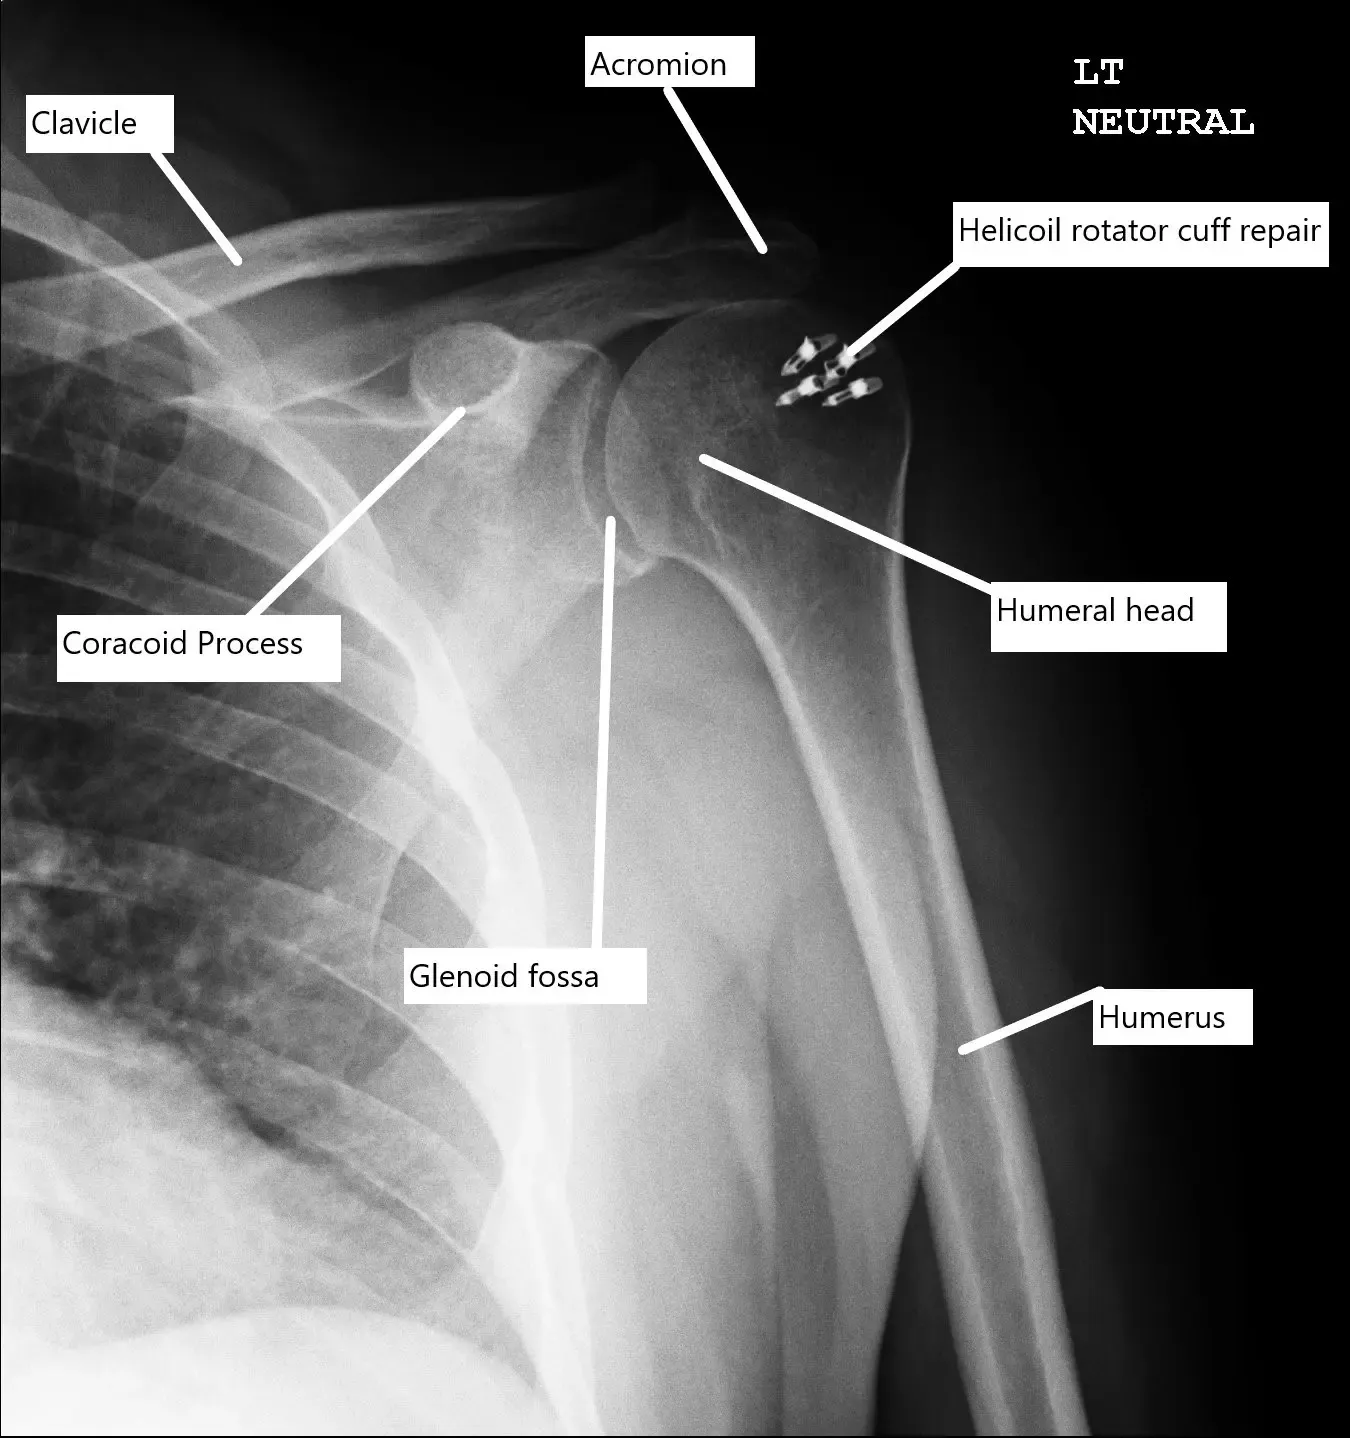

Postoperative X-ray of the shoulder with rotator cuff repair.

Then, a 4.5 mm Helicoil (S&N) with four tails was used and inserted into the humeral head following drilling and tapping. All the four tails were passed through the rotator cuff sequentially from the anterior to the posterior edge. The tails were tied over each over on to itself using a sliding knot.

The rotator cuff was well opposed. Final pictures were taken and saved. The shoulder was irrigated and drained.